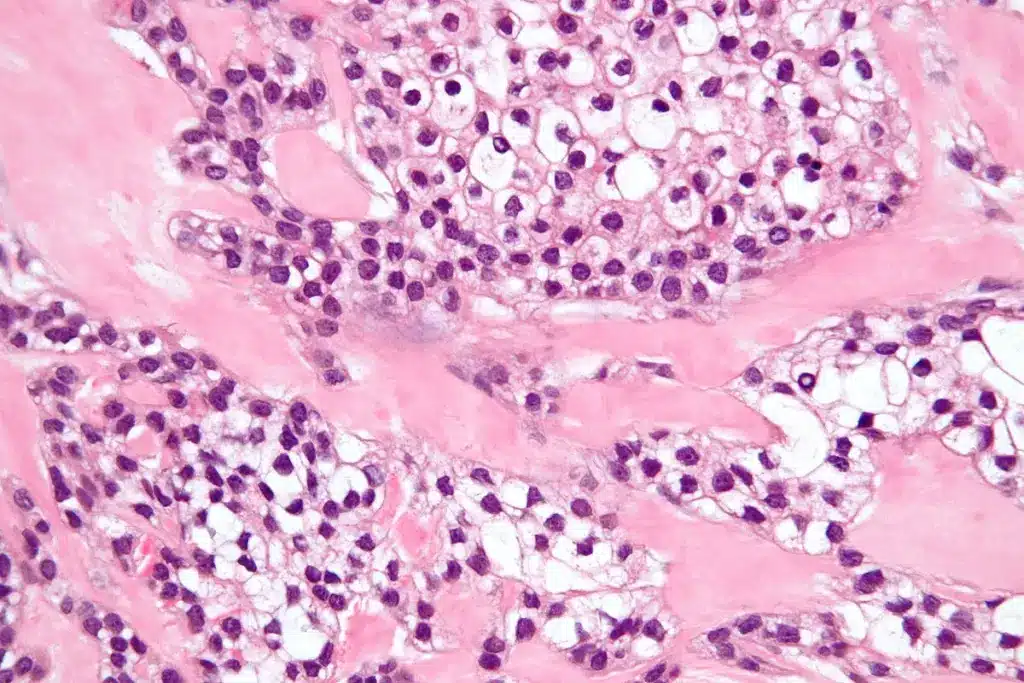

Squamous cell carcinoma (SCC) is a cancer that starts in squamous cells. These cells are flat and thin, found in the skin’s outer layer and some organs’ linings. It’s important to know about SCC because it’s common and can be serious.

Definition and Types of SCC

SCC happens when squamous cells grow out of control. There are different types, like:

Cancer Subtype and Differentiation

The subtype and differentiation of SCC are also important for prognosis. Well-differentiated SCC generally has a better outlook than poorly differentiated types. Knowing the cancer’s specific characteristics helps in choosing the right treatment.